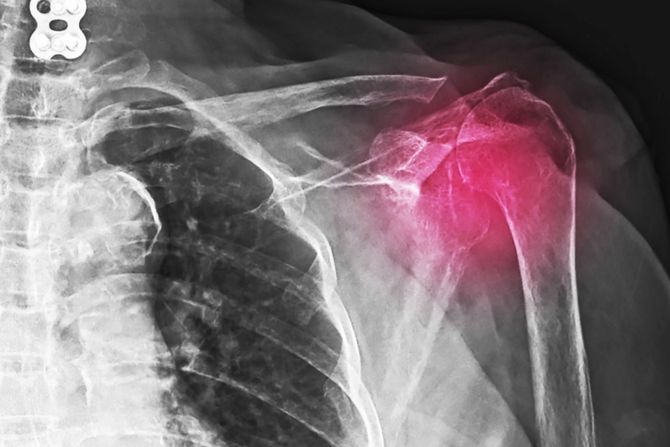

Ramena – Naslage kalcijuma u ​ ramenima mogu da izazovu bol i nelagodnost kada se krećemo, ali i  smanjen obim pokreta. Ali, ponekad kalcifikacija ramena ne izaziva simptome. Lekar može da ih otkrije tokom testa snimanja za sasvim nepovezano stanje. Stanje koje se naziva kalcifikacioni tendinitis razvija se kada se naslage kalcijuma nakupljaju u tetivama ili mišićima. Kalcifikacioni tendinitis može da se javi bilo gde u telu, ali najčešće pogađa rotatornu manžetnu. Rotatorna manžetna je grupa mišića i tetiva koje okružuju kuglu ramenog zgloba i drži kuglu ramenog zgloba u ramenskoj čašici.